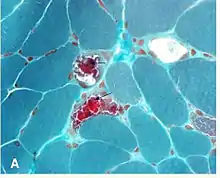

The "ragged red fibers" in MELAS syndrome are visible under modified Gomori stain.

Gömöri trichrome stain is a histological stain used on muscle tissue.[2][3]

It can be used to test for certain forms of mitochondrial myopathy.